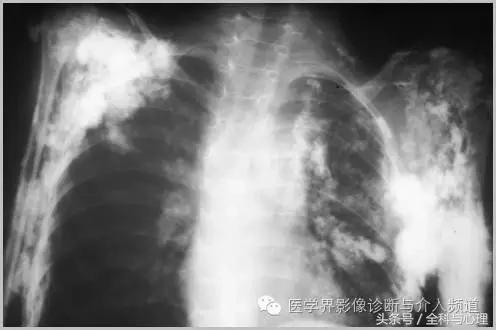

三、与胶原血管病相关的钙化

1、全身性钙质沉着症:皮肤、皮下或深部结缔组织钙化,与多种代谢紊乱及胶原血管病变有关,如皮肌炎,看起来像异位骨化,但没有真正的骨形成。开始为浅表的结节状或斑块状钙化,逐渐向更深的组织发展,表现为关节周围大片状钙化灶。

软组织钙化与骨化,软组织钙化和骨质增生 皮肌炎